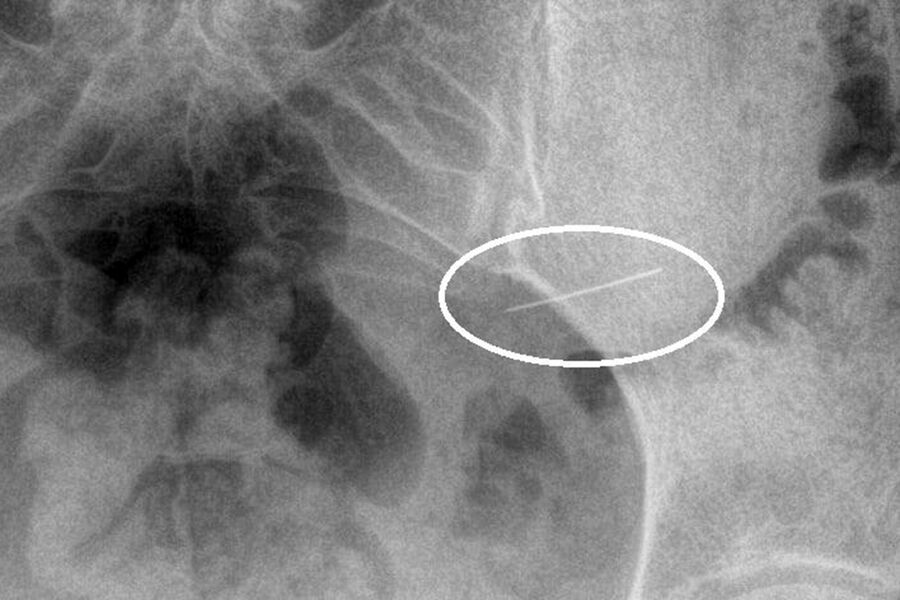

Пациентка вовремя обратилась за помощью, и бригада скорой доставила ее в стационар. Рентген брюшной полости показал инородное тело в желудке. Врачи первого хирургического отделения подготовили ее к экстренной операции, после чего с помощью современного оборудования эндоскописты аккуратно удалили опасный предмет, не допустив осложнений.